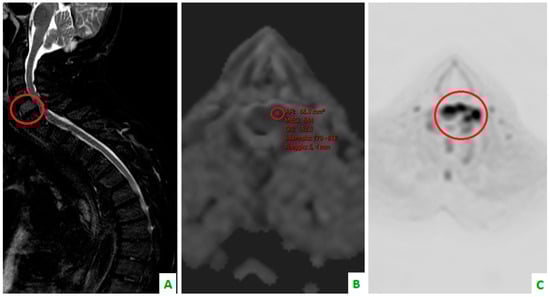

Figure 4. Focus on the red circles: (A) DIXON T2 weighted in the sagittal plane showing bone cervical metastasis (C5) (B) a low apparent diffusion coefficient (ADC) value in the same level, and (C) a restriction of diffusivity.

Skeletal metastases, which are predominantly osteolytic, localize in the spine in 50% of patients. This the most common area of localization, followed by the ribs (27.1%), ilium (10%), sacrum (7.1%), femur (5.7%), and the humerus, scapula, and sternum (2.9%). This is according to a retrospective study by Tsuya et al. [27] (Figure 3, Figure 4 and Figure 5).